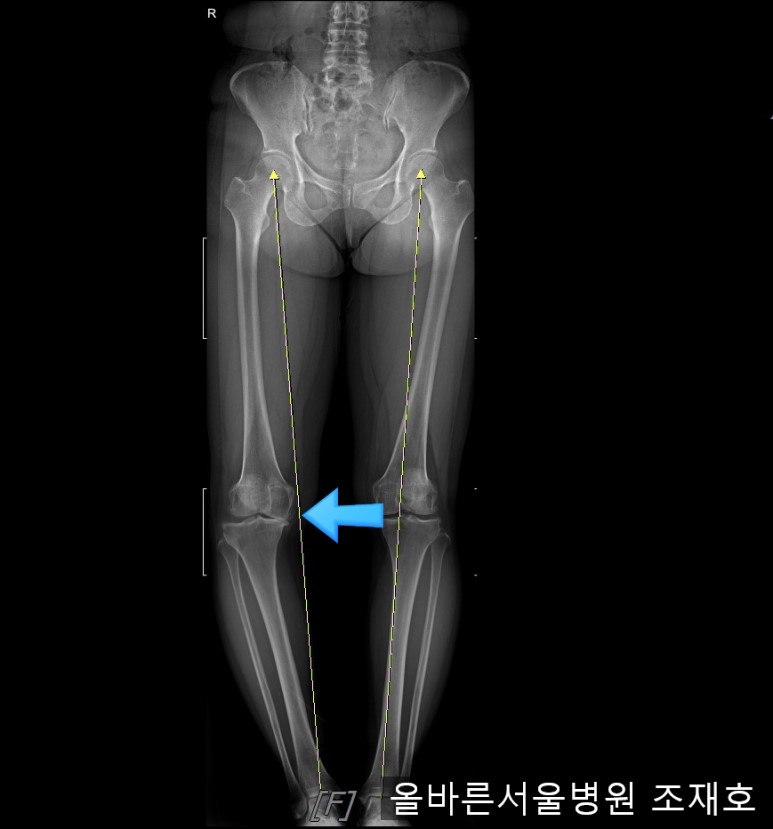

仅通过放射线片子观察到:右膝由于炎症严重,内侧胫骨及股骨已接触在一起,向内测严重变形。

左膝虽然也观察到了炎症,但远不如右膝严重。

如果通过X光片也观察到相同的病症,可以判断内侧关节的软骨大部分都损伤了。

观察膝盖下肢排列的扫描图像可看到右腿严重变形,身体中心向内倾斜。

这种状态下原本打算在其他医院做人工关节置换,后又到我院接受治疗。